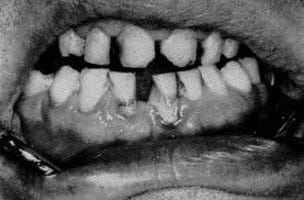

Lead sulphide at the gingival margin associated with lead poisoning

Fortunes were made by the few and lost by many, and there always loomed the specter of bellan, the local name for lead poisoning. The symptoms were elusive: muscular weakness about the feet and the wrists, which could be the fatigue of a man who had worked underground from dawn to dusk. At least, they hoped it was; but gradually they found they were unable to lift their pots of beer without pain. From the knees downwards they were afflicted with curiously persistent pins and needles. At night, in the light of tallow candle, they saw the reflection of that ominous blue line around their gums. They knew the acute gut-ache, that condition known as painters’ colic. They were in the grip of bellan. In some areas hens could not be kept because the grits they picked up contained fragments of lead, and the streams that poured out of the deep workings were covered over with slabs of limestone to prevent stock from drinking poisoned water.